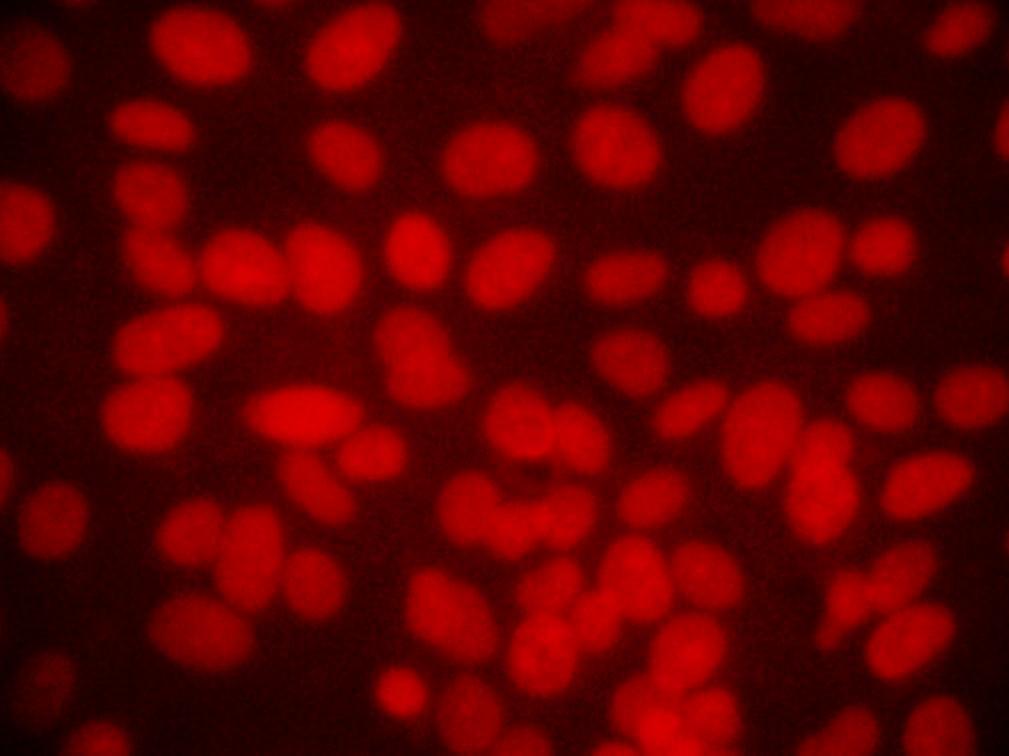

The fluorescence micrograph of the control and Silver nanoparticles treated Hep3B cells assessed for nuclear morphology after staining with propidium iodide stain. The control untreated Hep3B cells (Figure 5a) shows clear nuclei. The highly condensed and fragmented nuclei that are the index of apoptosis were observed in silver nanoparticles treated cell at different time point 24 h and 48 h (Figure 5b and c). The apoptotic nuclei after treatment with silver nanoparticles found to be increased in a time dependent manner which was clearly revealed by nuclear condensation and fragmentation.

Fig. 5a: Detection of Apoptosis Using PI staining- Hep 3B cell line control

Fig. 5b: 24 hrs after treatment of Hep 3B cell line with IC50 concentration, arrows indicates the cells with fragmented nuclei

Fig. 5c: 48 hrs after treatment of Hep 3B cell line with IC50 concentration, arrows indicates the cells with fragmented nuclei